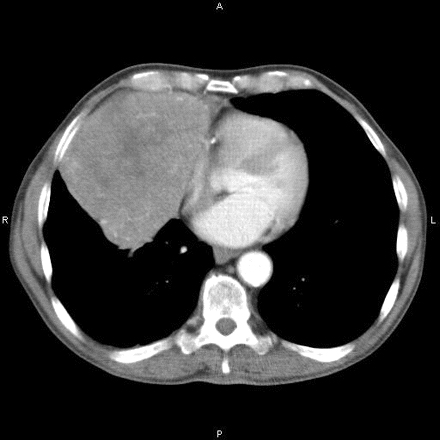

Tomografia computadorizada mostrando massa mediastinal anterior

Hamid UI, Jones JM. Mediastinal mass. BMJ Case Reports 2010 Oct 4;2010:bcr1120092471.